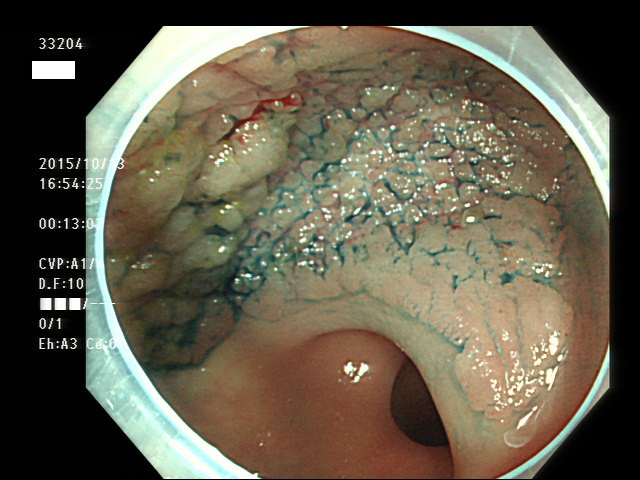

上記100名より抽出した平坦・陥凹型腺腫(=癌化の危険が高いが見落としやすい病変)の内視鏡写真